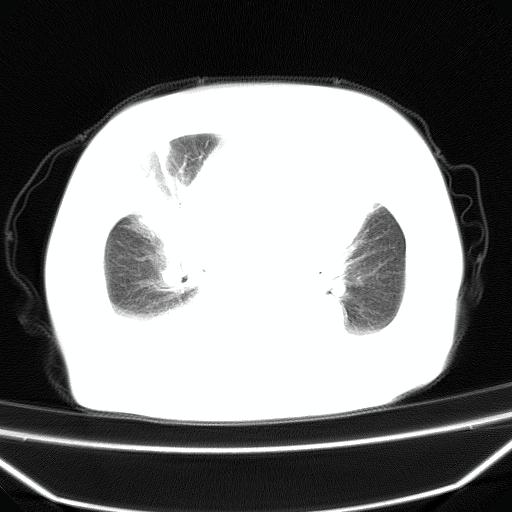

以下是引用jiangjing在2008-4-20 10:43:00的发言:[br]结合病史支持 冠心病[冠状动脉钙化],心功能不全,肺淤血、肺水肿,双侧胸腔与斜裂积液

以下是引用liuyue在2008-4-19 22:25:00的发言:[br]先考虑:1.心衰伴肺水肿、双侧胸腔积液、叶间积液、双下肺不完全性肺不张; [br] 2.冠状动脉粥样硬化。

以下是引用lijuanln在2008-4-19 23:05:00的发言:[br]两侧胸腔积液,肺水肿[br]心包积液[br]提示心衰